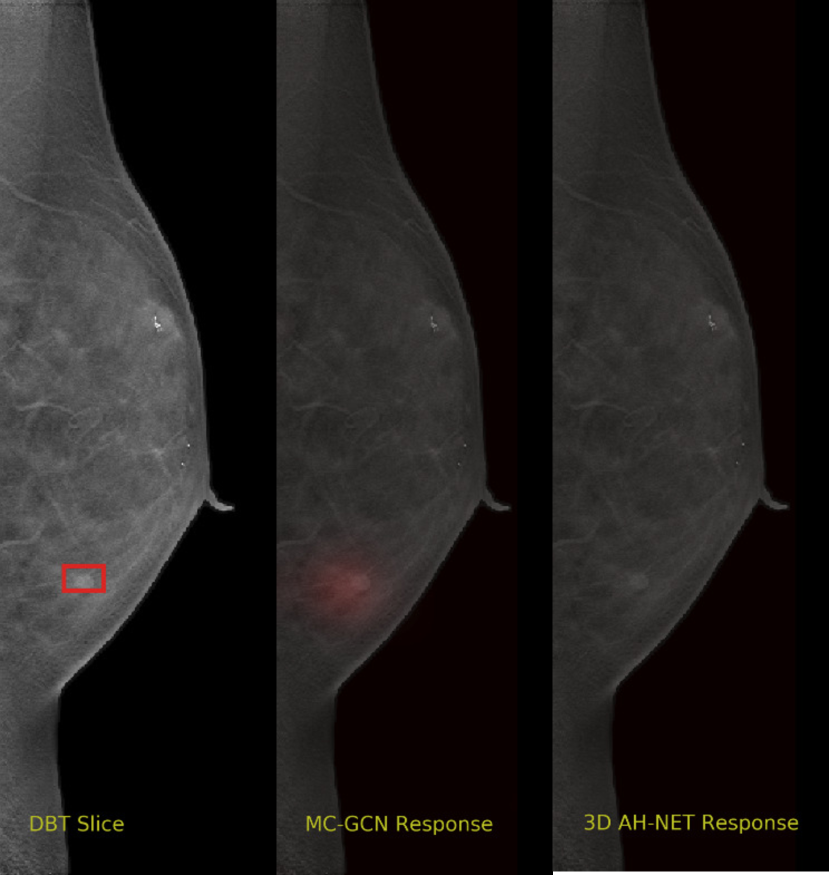

Appendix A Visual Cases of the DBT dataset

We selected some example slices from the DBT dataset to demonstrate the advantage of our proposed AH-Net for the Breast cancer screening. From Fig. 8 to Fig. 12, we show slices from five test DBT volumes that both the MC-GCN and the proposed 3D AH-Net could successfully detect the suspected breast lesion. The original DBT slice is shown on the left with the lesion annotated by our radiologist. Please note the original annotation is a 3D box. The figures in the middle and on the right are response maps from MC-GCN and 3D AH-Net overlaid on the original image, respectively. The detection locations obtained with non-maximal suppression are displayed with cross markers. As shown in the images, the proposed network can detect breast lesions varying in sizes and appearances. The confidence of the 3D AH-Net is usually higher than that of MC-GCN. From Fig. 13 to Fig. 17, we show five volumes that MC-GCN failed to detect the lesions since the lesions were not distinguishable from other breast tissues using the information within the slice. In contrast, 3D AH-Net was able to detect the lesions from such volumes using the 3D context between slices. As shown in Fig. 18 to Fig. 22, there are also volumes with lesions that both network failed to detect. Such lesions normally reside in the dense breast tissues. The boundary between these lesions and the normal breast tissues usually have low contrast. The networks sometimes also confuse them with other roundish structures in the breast such as lymph nodes or skin moles.

Refer to caption

Figure 13: Example DBT slice 6 with a lesion that can only be detected by 3D AH-Net. The lesion is highly blended within the dense breast tissues which makes it challenging for both the radiologists and the networks to detect through a single slice. In contrast, the lesion can be detected by considering the consistency of the structure across a few neighbouring slices.